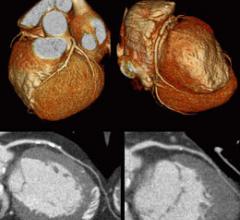

The cardiac imaging channel includes the modalities of computed tomography (CT), cardiac ultrasound (echocardiography), magnetic resonance imaging (MRI), nuclear imaging (PET and SPECT), and angiography.

There are currently three major trends in cardiovascular computed tomography (CT) technology — lowering radiation dose ...

Two big advances in cardiac advanced visualization software were highlighted in December at the 2010 Radiological ...